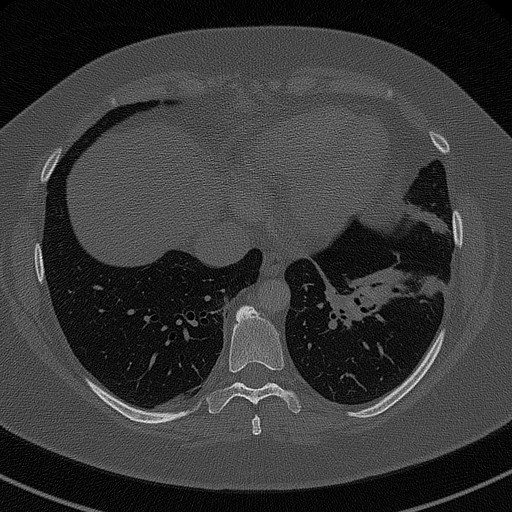

lungs HR 00000020